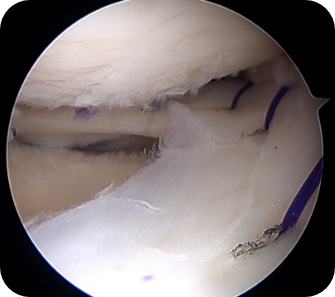

• 1) 관절경하 연골판 부분절제술

반월상 연골판 파열이 일어난 경우, 파열된 조각에 의해 관절연골이 긁혀 통증을 유발하거나 관절염이 진행될 가능성이 높을 때, 문제가 되는 연골판 부분만 절제해 주는 방법입니다. 파열된 연골판 조각이 기능을 못한다고 판단될 경우에 적용됩니다.

수술방법

관절내시경을 이용하여 무릎 안을 보면서 여러 기구를 이용하여 문제가 되는 부분만을 제거합니다.

• ▲ 무릎 연골판 부분절제술 전

• ▲ 무릎 연골판 부분절제술 후

수술장점

수술 후 특별한 운동의 제한이나 목발-보조기 등이 필요가 없습니다. 물론 동반된 다른 손상이 있어 그에 대한 치료를 할 때에는 그에 대한 재활 기간을 요합니다. 한계점으로 연골판의 결손부위가 생기는 것으로 연골판의 가장 중요한 기능인 충격 흡수, 연골의 손상예방 등에 문제가 발생합니다. 그러므로, 이미 파열된 부분이 기능을 하지 못할 때, 더 큰 손상을 일으킬 가능성이 높은 경우에만 부분제거를 고려합니다.

수술 후 관리법

간단한 내시경 수술로 수술 후 2주간은 수술부위 소독치료를 받아야 합니다. 목발 및 보조기 치료는 특별한 경우 외에는 필요하지 않습니다. 수술 다음날부터 일상생활에 문제없이 보행 및 활동 가능합니다. 부종 및 통증의 유무, 지속기간, 동반 손상 정도에 따라 차이가 있지만, 일반적으로 2주 ~ 2달 이내에 정상생활 및 운동으로의 복귀가 가능합니다.